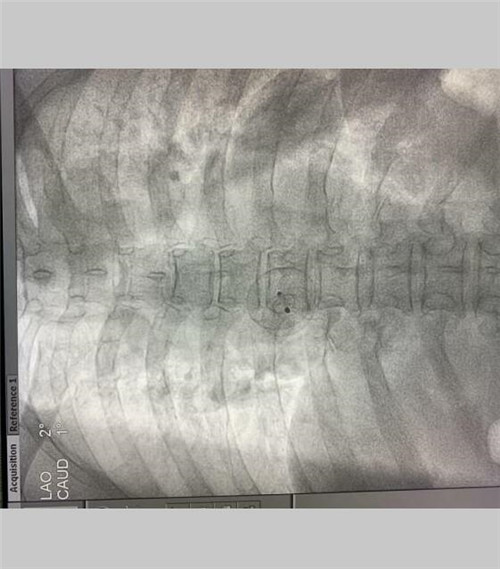

患者女性,62岁,入院时自述活动后心悸、乏力12年。入院后行心脏超声提示:房间隔缺损(继发孔型) 房水平左向右分流。在李军农主任的主持下,组织全科室医护人员,经过充分而全面的术前评估及准备,5月15日下午在介入科,在心脏超声指导下行房间隔缺损封堵术,手术用时35分钟,过程顺利。术后第2天下床活动,术后第3天出院。

术后一周门诊随访,心脏超声提示:房间隔无分流,封堵器位置正常。患者自诉再未发生活动后心悸、乏力不适,状态良好。